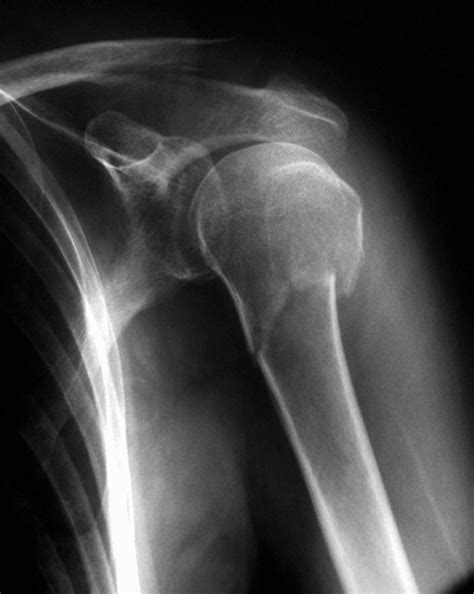

Capsulitis Hombro Después De Operación, La congelación del hombro porque sí, 21.13 MB, 15:23, 82,904, EFEsalud, 2019-01-10T16:24:29.000000Z, 3, HOMBRO CONGELADO O CAPSULITIS ADHESIVA - ALAI, www.alaismc.com, 1715 x 1704, jpeg, WebHombro congelado o capsulitis Uno de los problemas más frecuentes tras una operación de hombro es la rigidez de la articulación del hombro . En algunas intervenciones quirúrgicas es necesario un periodo de inmovilización para permitir una. WebLa capsulitis adhesiva retráctil, o más comúnmente conocida como hombro congelado, es un proceso que se caracteriza por la inflamación y retracción de toda esta cápsula. WebLa capsulitis adhesiva provoca una disminución progresiva del rango de movimiento del hombro, tanto activo como pasivo, que acaba afectando de manera., 20, capsulitis-hombro-despues-de-operacion, Novedades y Muebles WebHombro congelado o capsulitis Uno de los problemas más frecuentes tras una operación de hombro es la rigidez de la articulación del hombro . En algunas intervenciones quirúrgicas es necesario un periodo de inmovilización para permitir una. WebLa capsulitis adhesiva retráctil, o más comúnmente conocida como hombro congelado, es un proceso que se caracteriza por la inflamación y retracción de toda esta cápsula. WebLa capsulitis adhesiva provoca una disminución progresiva del rango de movimiento del hombro, tanto activo como pasivo, que acaba afectando de manera.

WebLa capsulitis adhesiva retráctil, o bien más generalmente conocida como hombro congelado, es un proceso judicial que se caracteriza por la inflamación y retracción. WebEl hombro congelado también conocido como capsulitis adhesiva es una inflamación y retracción de la capsula articular que envuelve el hombro y que causa la pérdida de. WebLa capsulitis adhesiva idiopática, u hombro congelado, debe diagnosticarse de forma temprana y correcta. Se trata de una pérdida global de movimiento glenohumeral. WebEn cuanto al inicio de síntomas en el hombro izquierdo, busque de nuevo la posibilidad de la Fisioterapia pero con esa condición ya dicha de que sea suave y progresiva.. Si. WebEl dolor en la articulación del hombro y el rango limitado de movimiento son los mayores problemas resultantes de la capsulitis adhesiva. La capsulitis adhesiva. WebLa capsulitis adhesiva, normalmente, comienza de forma muy lenta y tiene tres fases bien definidas que, combinadas, pueden durar hasta 3 años: Fase. WebCAPSULITIS ADHESIVA . Denominada también como hombro congelado o pericapsulitis, puede ser primaria o secundaria a diversas causas: traumatismo,.